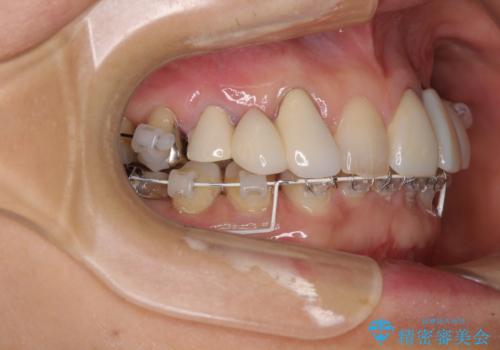

- 割れていると言われて放置してしまった歯や、前歯のデコボコなどが気になるとのことで来院された患者様です。

左上の歯は割れてしまっており、抜歯のうえインプラント治療が必要であり、他にも抜歯の必要な歯がある状態でした。

上顎はほぼ全ての歯をセラミッククラウンにて補綴治療を行う必要があるため、気になるデコボコや深い咬み合わせを改善するために下顎と上顎の臼歯部の矯正治療を行うこととしました。

過蓋咬合(下顎前歯が隠れてしまうほどの深い咬み合わせ)のため、スムーズに歯が動かず矯正治療に時間がかかりましたが、無事に仕上げることができました。